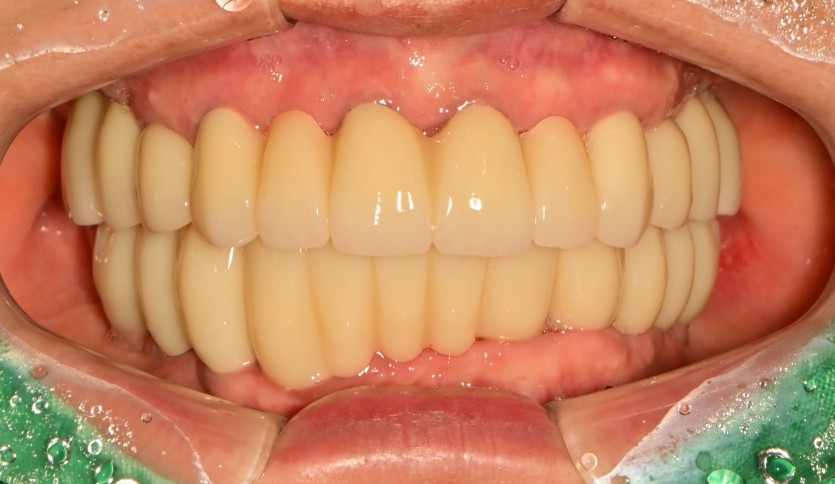

만 61세 전체 임플란트 증례

전체 임플란트 증례입니다.

18개의 임플란트로 완성하였습니다.